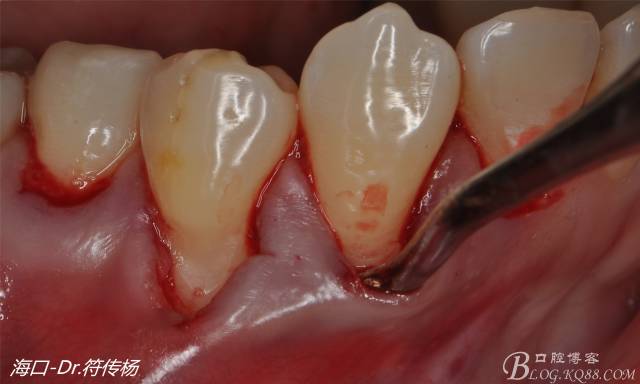

首先用顯微手術(shù)刀切斷手術(shù)范圍內(nèi)的牙周韌帶

然后使用下頜開隧刀剝離牙齦

最后使用牙齦乳頭分離器分離牙齦乳頭